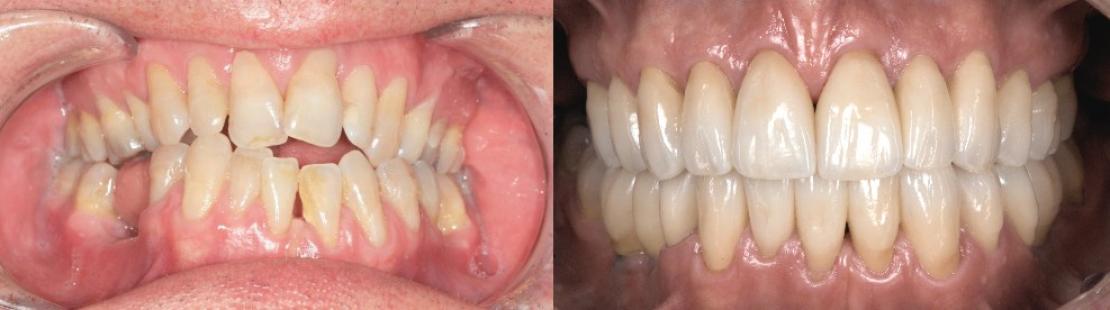

En fin de traitement pré-prothétique, une analyse globale de la nouvelle situation est réalisée pour élaborer un plan de traitement prothétique. Bien que l’occlusion obtenue soit stable et fonctionnelle, le sourire du patient reste disgracieux. La présence de trous noirs interproximaux, des anomalies de proportions, de nombreux composites de collet ainsi que quelques mylolyses restent préjudiciables au niveau esthétique.

Pour finaliser le plan de traitement, une simulation numérique du projet esthétique est réalisée, à partir d’une analyse photo et vidéo du sourire. La séquence vidéo assure une meilleure évaluation de la dynamique dento-labiale lors de la phonation. Elle précise également le sourire Duchenne du patient et donc le positionnement le plus haut de sa lèvre supérieure. Un wax-up, réalisé par le prothésiste à l’aide du projet virtuel, permet de le visualiser en bouche avec un mock-up. Après validation, les pièces partielles en céramiques collées sont élaborées. Du fait des récessions, les limites de préparation présentent des plages avec peu, voire pas d’émail. Une attention particulière est apportée au protocole de collage, effectué sous digue, avec un MR3 par mordançage, rinçage puis application séparée de primer et d’adhésif avant de coller avec un composite dual.